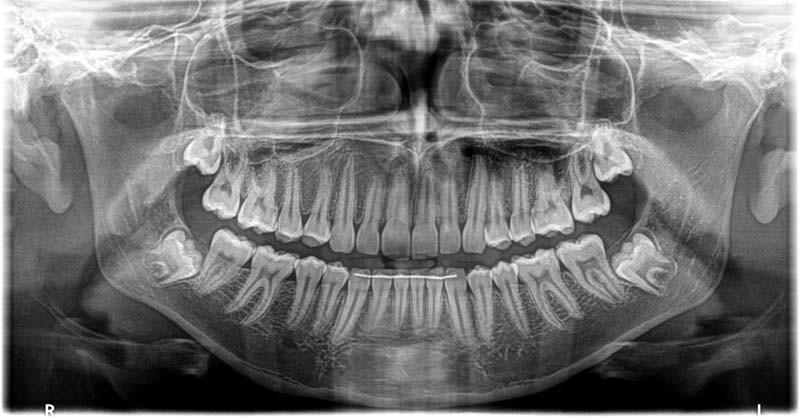

- Panoramică – imagine de ansamblu a ambelor arcade